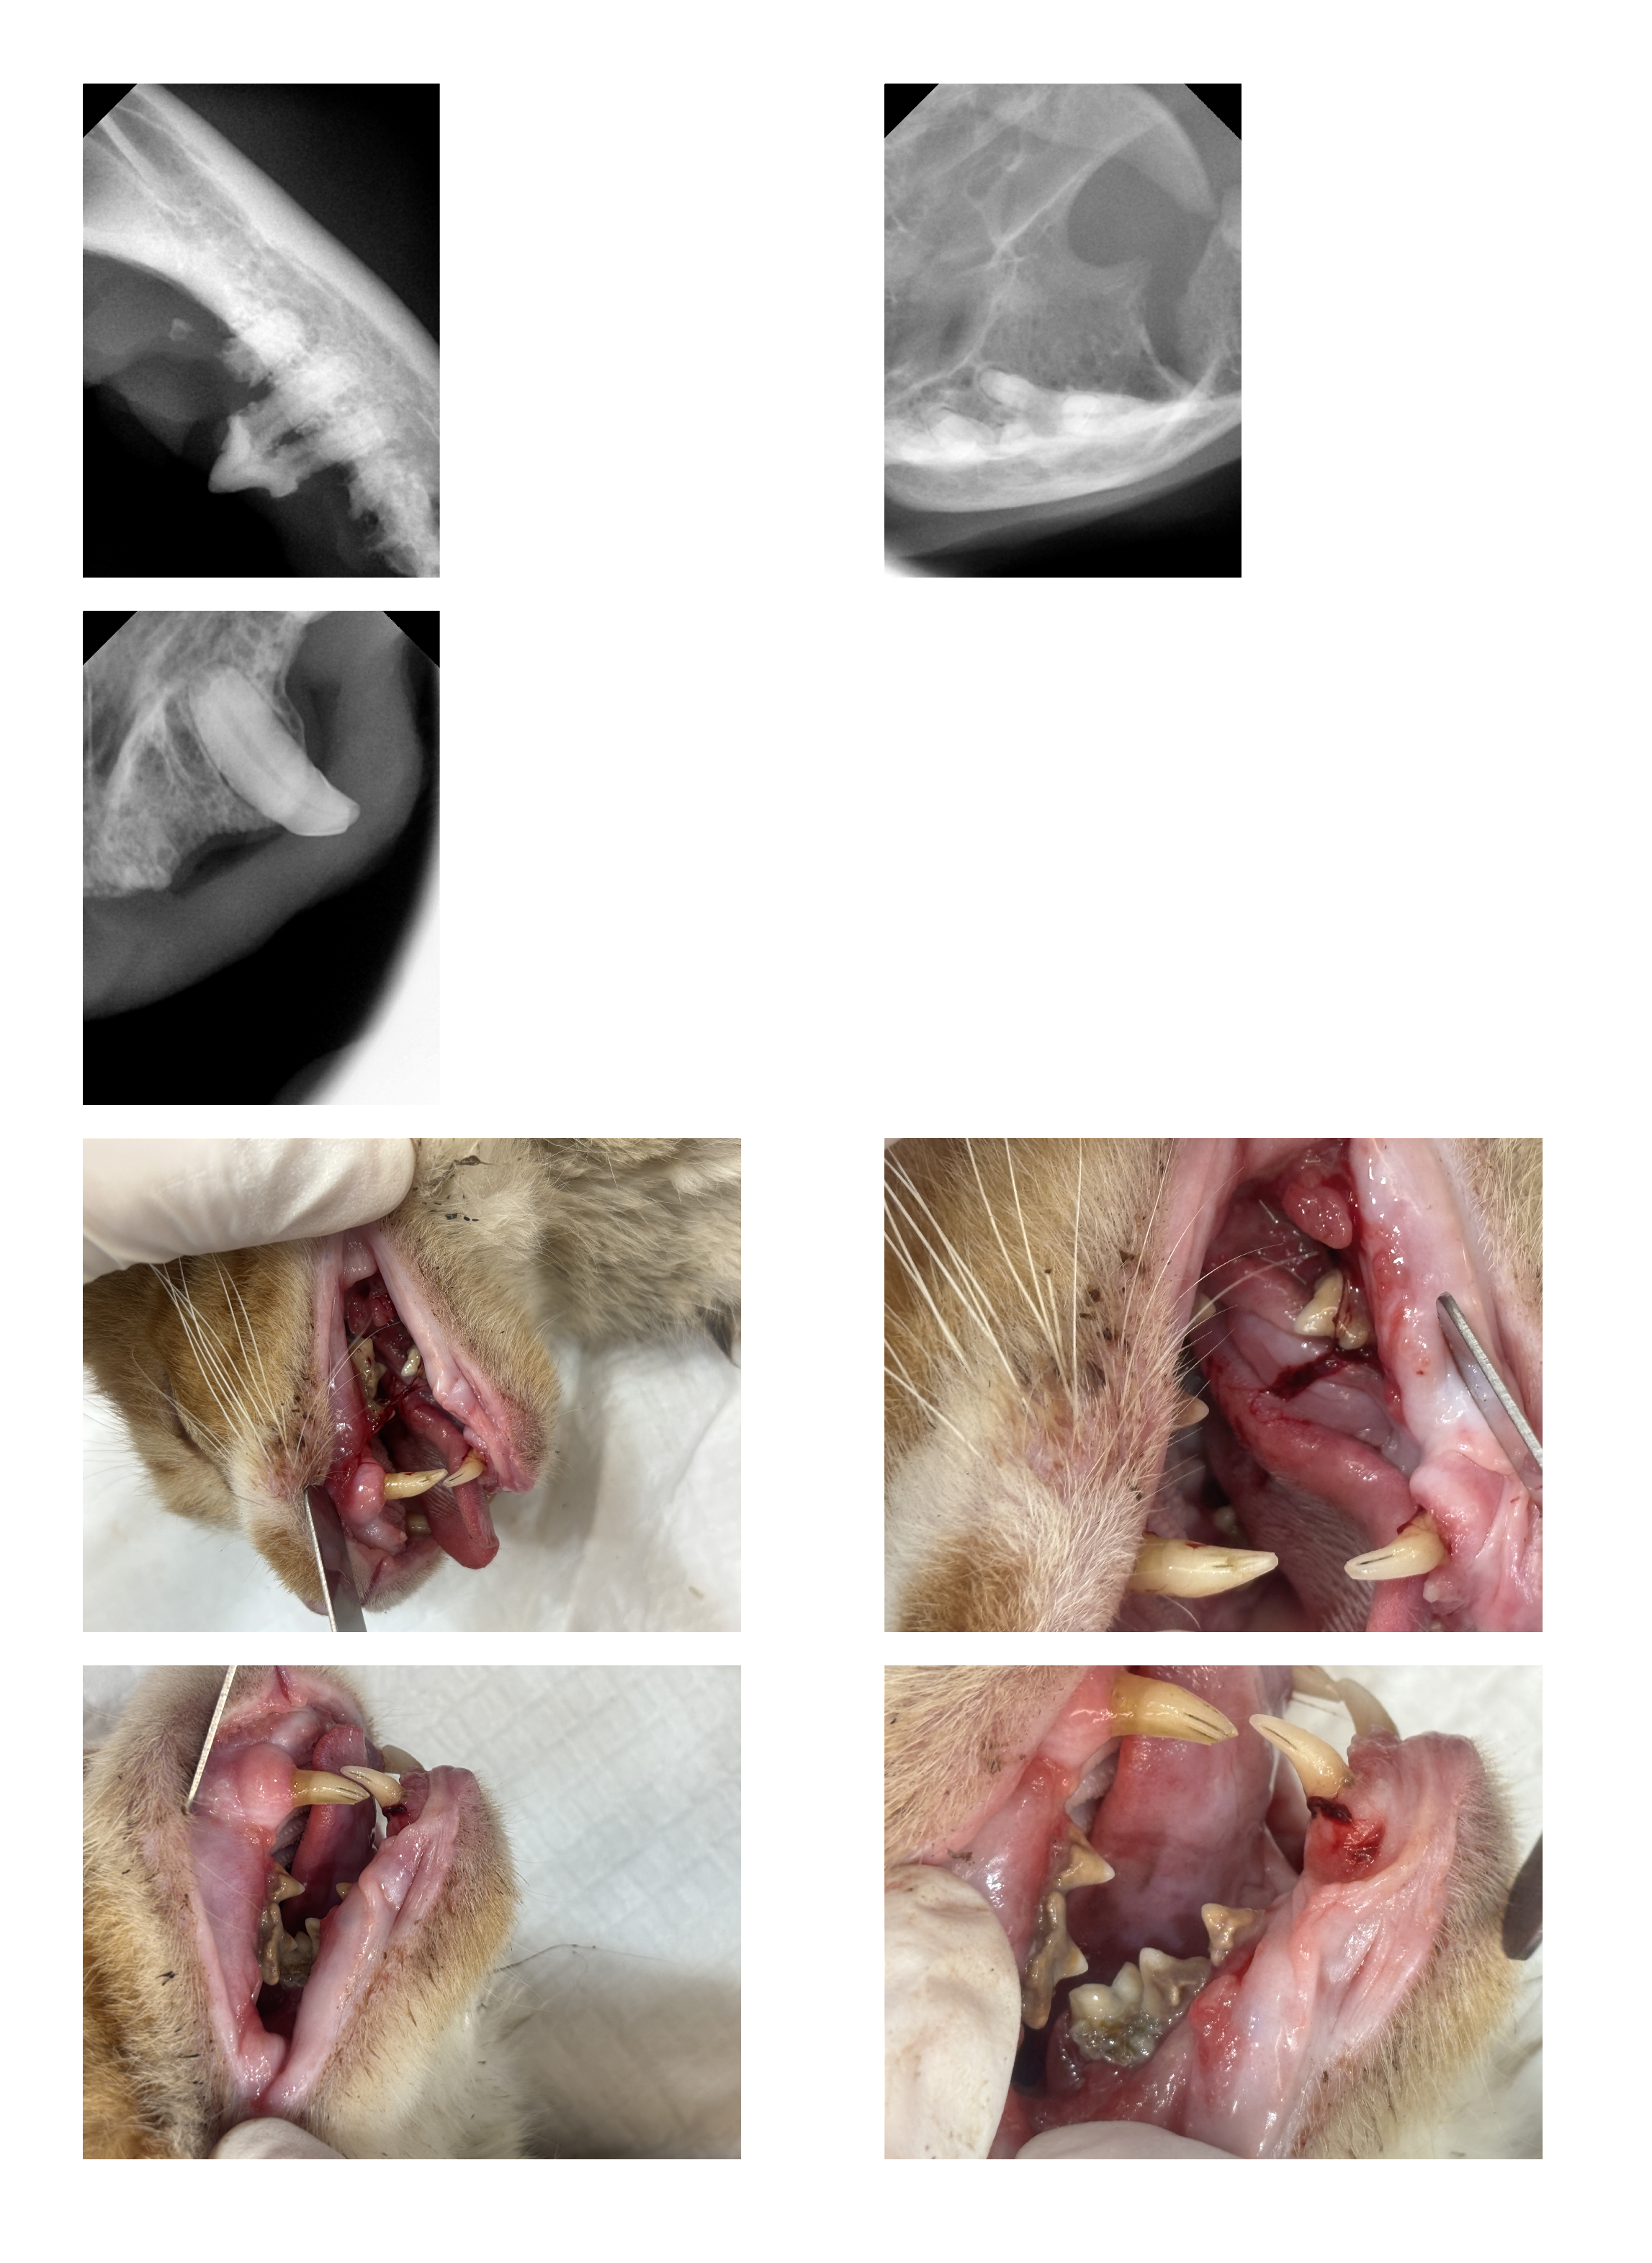

| 치료과정 | 호빵이는 저녁에도 습식을 먹으러 매일 나오지는 않던 녀석이라 구조가 걱정이었습니다. 습식 시간에 나타나길 기다리다가 한 차례 구조에 실패해 마음을 졸이게 했지만, 겨울집이나 여름집을 마련해 두는 곳에는 잘 머무르곤 했기에 이튿날인 10월 21일(화) 낮에 급식소와 집을 마련해 둔 곳 근처에 포획틀을 설치했고 무사히 구조할 수 있었습니다. 미리 연락해 둔 병원으로 곧바로 이동하였고, 사납고 사람 손을 타지 않는 성격인 터라 마취한 후 대기 시간을 가진 후 본격적인 검사에 들어갔습니다. 이 병원에서는 마취 후 상태를 보고 발치가 필요한지 아닌지를 판단한다고 하였는데요, 호빵이는 오랫동안 구내염을 앓아 왔기에 전발치가 필요한 상태임을 진단받았습니다. 그렇게 당일 모든 이빨에 대한 전발치를 진행하였고, 특히 목 안쪽에 염증이 심했던 상태라 조금 편하게 호흡을 할 수 있도록 추가적인 처치를 해 주셨다고 했습니다. 또 2주 동안 효과가 지속되는 항생제 처치도 진행하였습니다. 불행 중 다행히도 혈액 검사 결과 별다른 문제는 더 발견되지 않았습니다. 병원 방침상 발치 후 당일 퇴원한다고 하였으나, 힘든 수술을 한 아이를 바로 방사할 수는 없어 하루 동안 입원을 부탁드렸고 다음 날인 10월 22일(수) 오전에 호빵이를 데려와 원래 지내던 곳에 제자리 방사하였습니다. |

| 대상묘 치료중 사진 |     |

앗 중간에 올린 사진들이 다 첨부가 안 된 것 같네요..ㅠㅠ

치료 전 대상묘 사진 / 대상묘 치료중 사진 / 치료 완료 후 사진 다시 올려 봅니다!

[치료 중 사진]